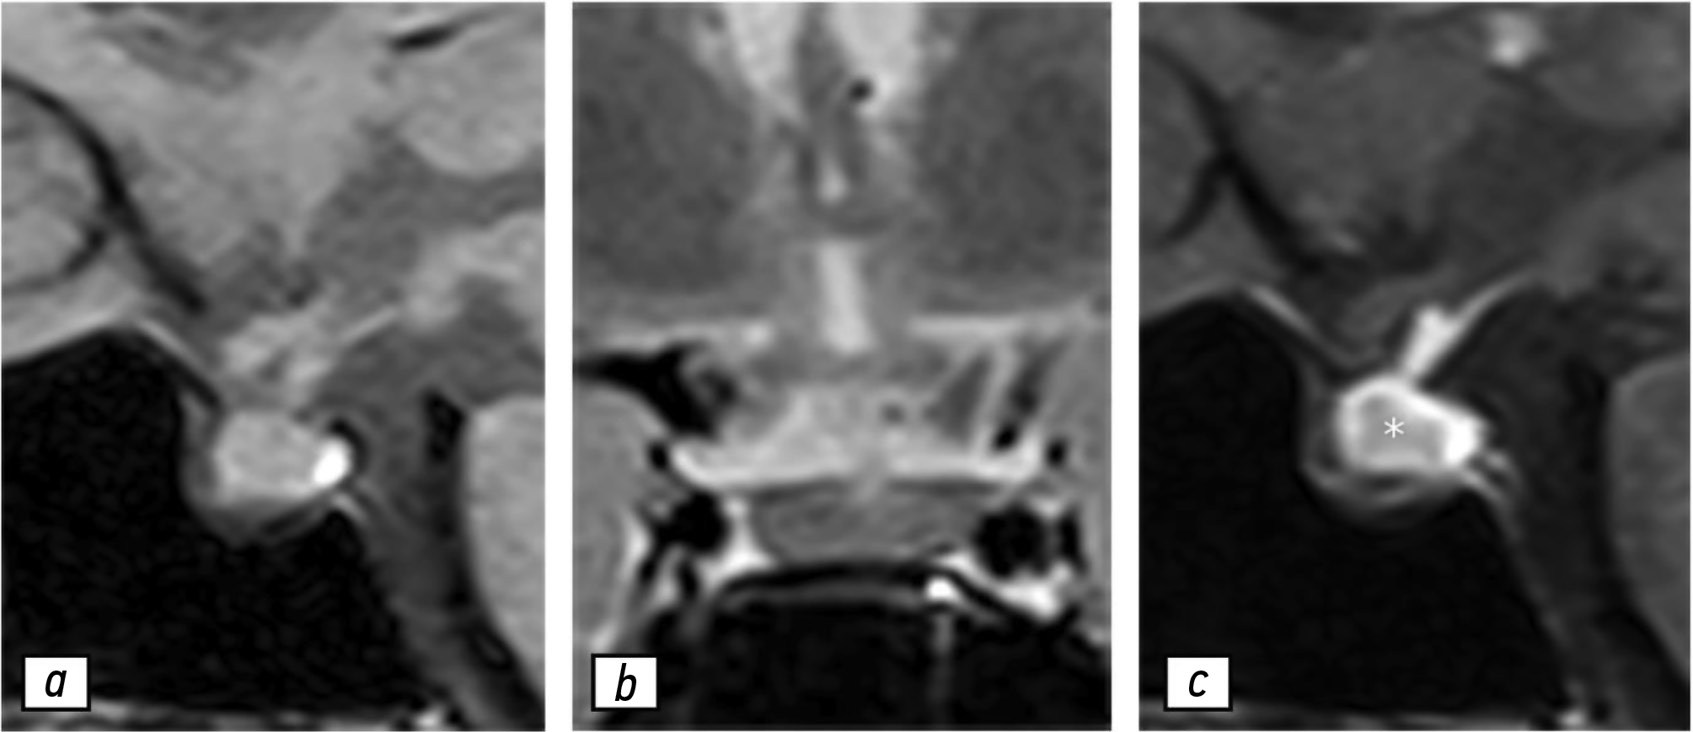

Magnetic resonance imaging in prenatal diagnosis of tuberous sclerosis complex: a case report

Early detection of orphan diseases, including tuberous sclerosis complex, requires a multidisciplinary approach and the integration of new prenatal diagnostic methods, utilizing ultrasound and magnetic resonance imaging. Accumulated knowledge of the clinical manifestations of tuberous sclerosis complex and advancements in diagnostic techniques enable the identification of this condition. Magnetic resonance imaging allows for high-quality anatomical and functional imaging of the brain in various planes, improving the sensitivity and diagnostic value of the method for early (prenatal) detection of cerebral manifestations of tuberous sclerosis complex. Additionally, magnetic resonance imaging detects mediastinal masses. This highlights the need for a comprehensive approach in diagnosing tuberous sclerosis complex, with magnetic resonance imaging as the primary method for assessing the fetus’s cardiovascular and central nervous systems.

This article presents a clinical case of tuberous sclerosis complex determined by intrauterine diagnosis followed by postnatal examination of the newborn and genetic confirmation of the diagnosis. This case report demonstrates the diagnostic value of magnetic resonance imaging in the prenatal diagnosis of tuberous sclerosis complex.